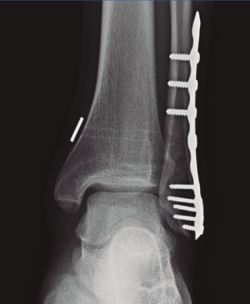

- Rotura o aflojamiento (Figura 2). Relacionada con no retirarlo, pero sin aparentes resultados negativos funcionales(15,16).

Figura 2. Fractura del maléolo peroneo sintetizada con placa anatómica y tornillo transindesmal roto a los 6 meses de seguimiento con mantenimiento de la reducción de la sindesmosis.